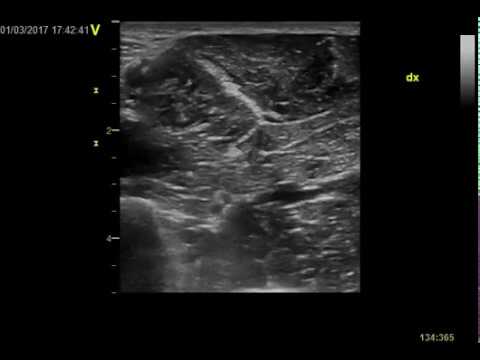

Anterior interosseous with median nerve at pronator exit. Normal nerve ultrasound.

Anterior interosseous enlargement at pronator exit. Nerve ultrasound.